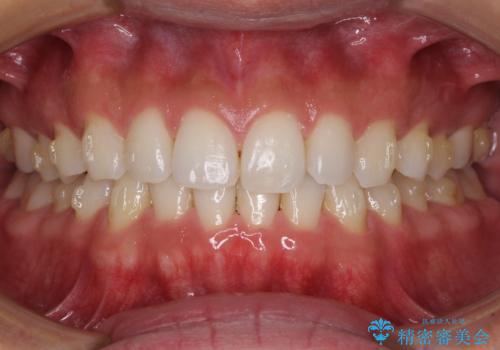

- 上下前歯のデコボコを気にして来院された患者様です。

以前矯正をした後戻りということで、歯列不正はそれほど大きくなかったため、インビザライン・ライトを用いて矯正治療を行うこととしました。

1日22時間以上しっかりと装着してくださったので、半年かからずに治療を終えることができました。